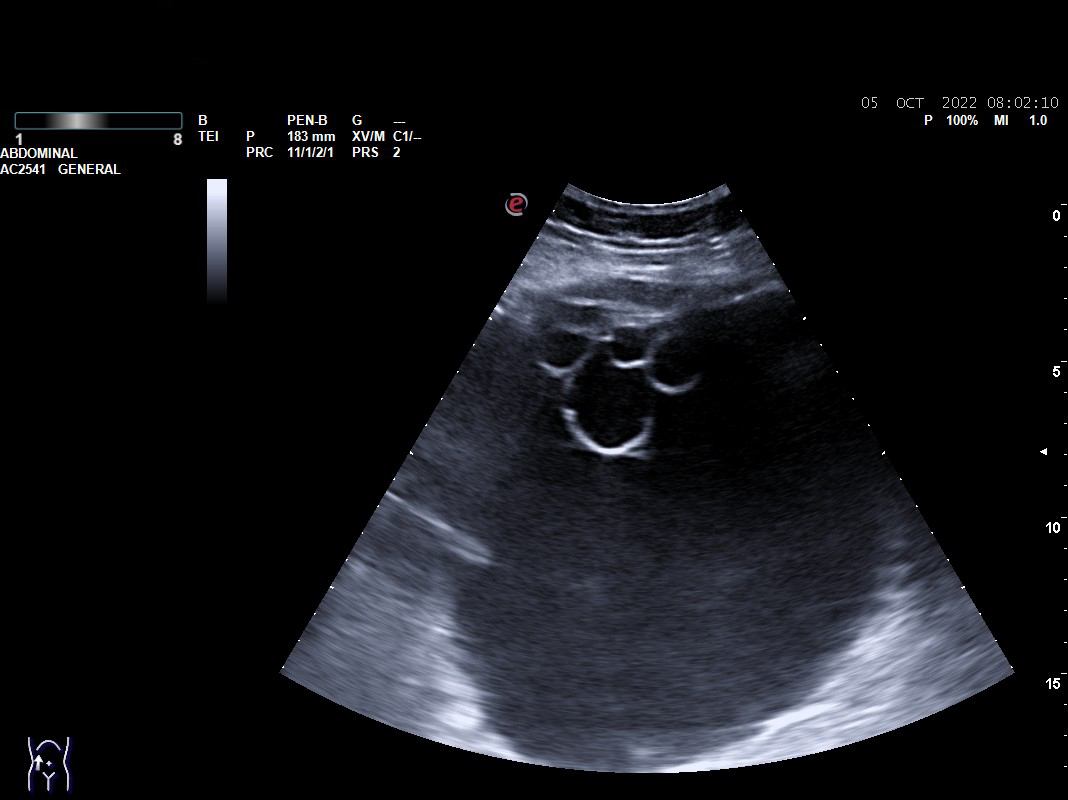

Objetivamos formación quística compleja tabicada de 17 x 10 cm con cámaras en su interior que parece depender de ovario, sin vascularización. Presencia de líquido libre en Douglas.

Con sospecha de formación anexial se deriva a Urgencias de Ginecología para valoración: exploración ginecológica normal y en Eco-Doppler-Transvaginal confirman formación multicameral sonoluscente localizada en zona central de pelvis, suprauterina hasta un través por encima de ombligo, ocupando toda la pelvis de 176 x 107 mm con múltiples cámaras en polo superior derecho. No se visualiza líquido libre en hemiabdomen superior, no impresiona de carcinomatosis  ni de dilatación de pelvis renales. Líquido libre en Douglas moderado. Sin ascitis.